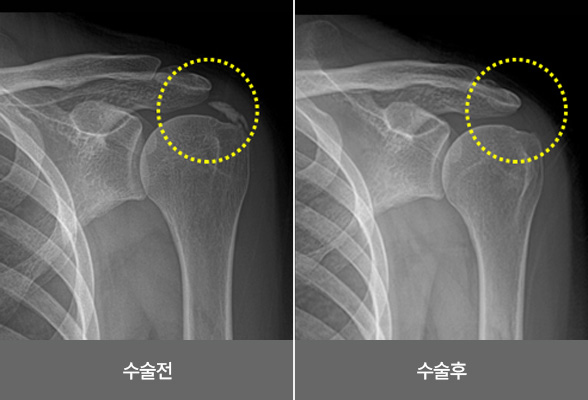

어깨 충돌 증후군

어깨를 회전시켜주는 근육인 회전근개와 어깨 관절을 덮고 있는

견봉 사이의 간격이 좁아지고 서로 충돌하면서 염증을 일으키고 통증이 발생되는 질환입니다.

어깨 충돌 증후군의 증상

비수술 치료 : 약물, 고정치료 (깁스 또는 보조기), 물리치료, 주사치료, 도수치료

수술치료 : 견봉 성형술